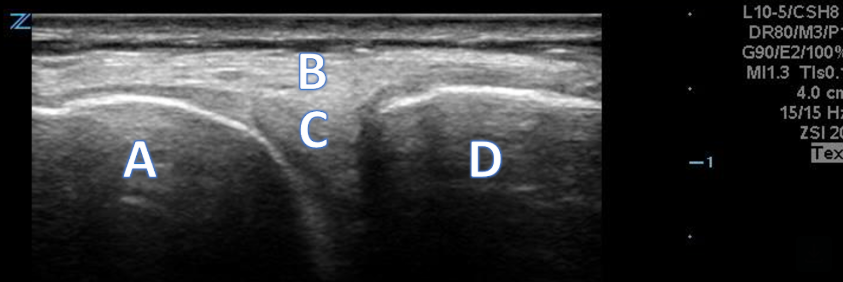

A 66-year-old male with right anterior elbow pain, ecchymosis, and a “lump” in his right upper extremity after a ground level fall.